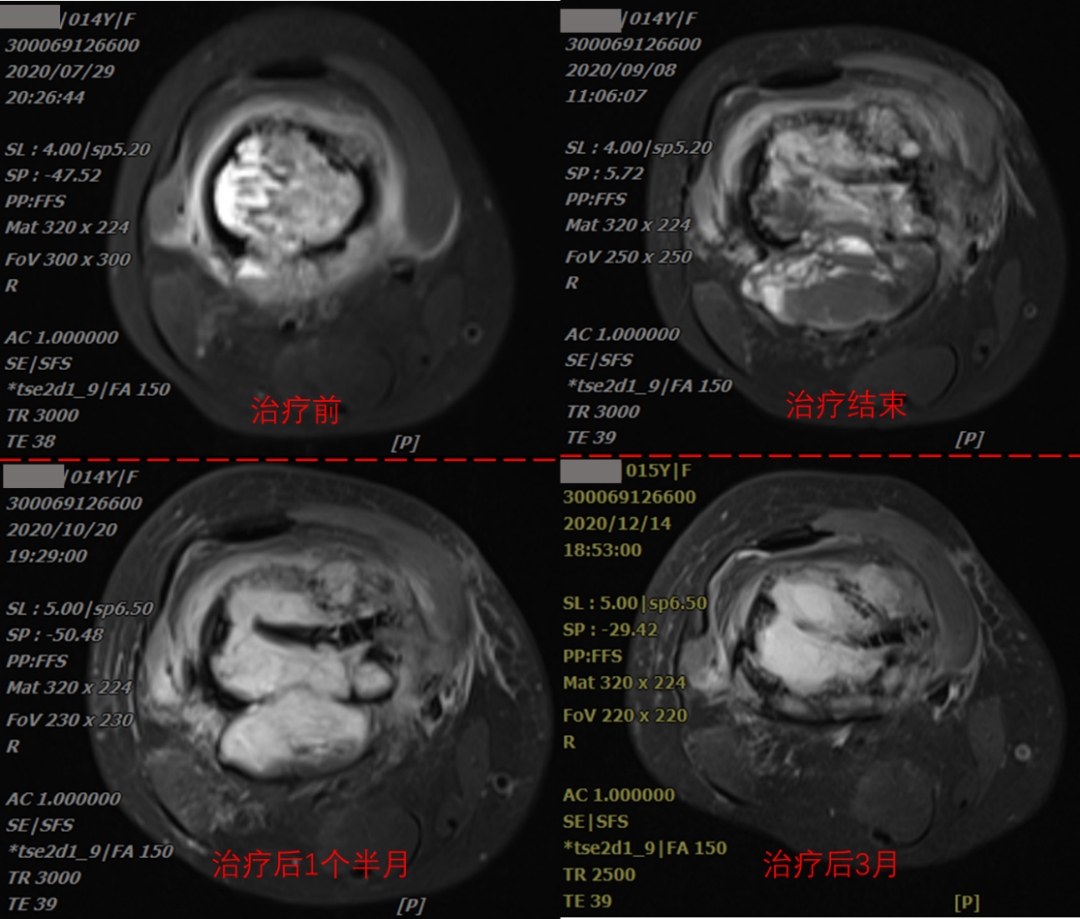

The patient, a 14-year-old female, was presented with the main complaint of "right thigh pain with mobility disorder for 3 months". CT examination indicated mild dilatant bone destruction in the right lower femur, accompanied by periosteum hyperplasia and soft tissue swelling, and neoplastic lesions (about 3.6x12.1x4.9cm in size) were mainly considered. Biopsy of the right femur mass was performed, and the biopsy results showed osteosarcoma (right lower femur). Diagnosis: osteosarcoma of right femur (cT2N0M0 Stage IIB KPS score: 70). The comprehensive treatment based on carbon ion radiotherapy was started on August 18, 2020. The tumor volume was 188.62cm3, and the heavy ion therapy was completed 12 times in total within three weeks. The treatment will end on September 3, 2020.

As can be seen from imaging data, tumor inactivation and slow absorption after treatment. According to international experience, it may take 1-2 years for huge sarcomas to be completely absorbed after inactivation. However, after heavy ion treatment, the purpose of limb preservation can be achieved, and anti-tumor immunity can be activated, and distant and side effects can be induced, which can effectively remove tumor tissue outside the tumor body. Combined treatment with chemotherapy and immunotherapy is expected to achieve a better effect, providing a new way for osteosarcoma patients. Through the observation of the treatment process of the patient's osteosarcoma, it can be seen that 1 and a half months after the end of heavy ion treatment of osteosarcoma, the local edema of the tumor was obvious, and 3 months after the end of the treatment, the local tumor was significantly smaller than before the treatment, the patient's symptoms were significantly relieved, and the tumor was well controlled locally. During the treatment, there was no obvious pain, no obvious edema in the lower extremities, and no obvious radiotherapy reaction in the local skin.